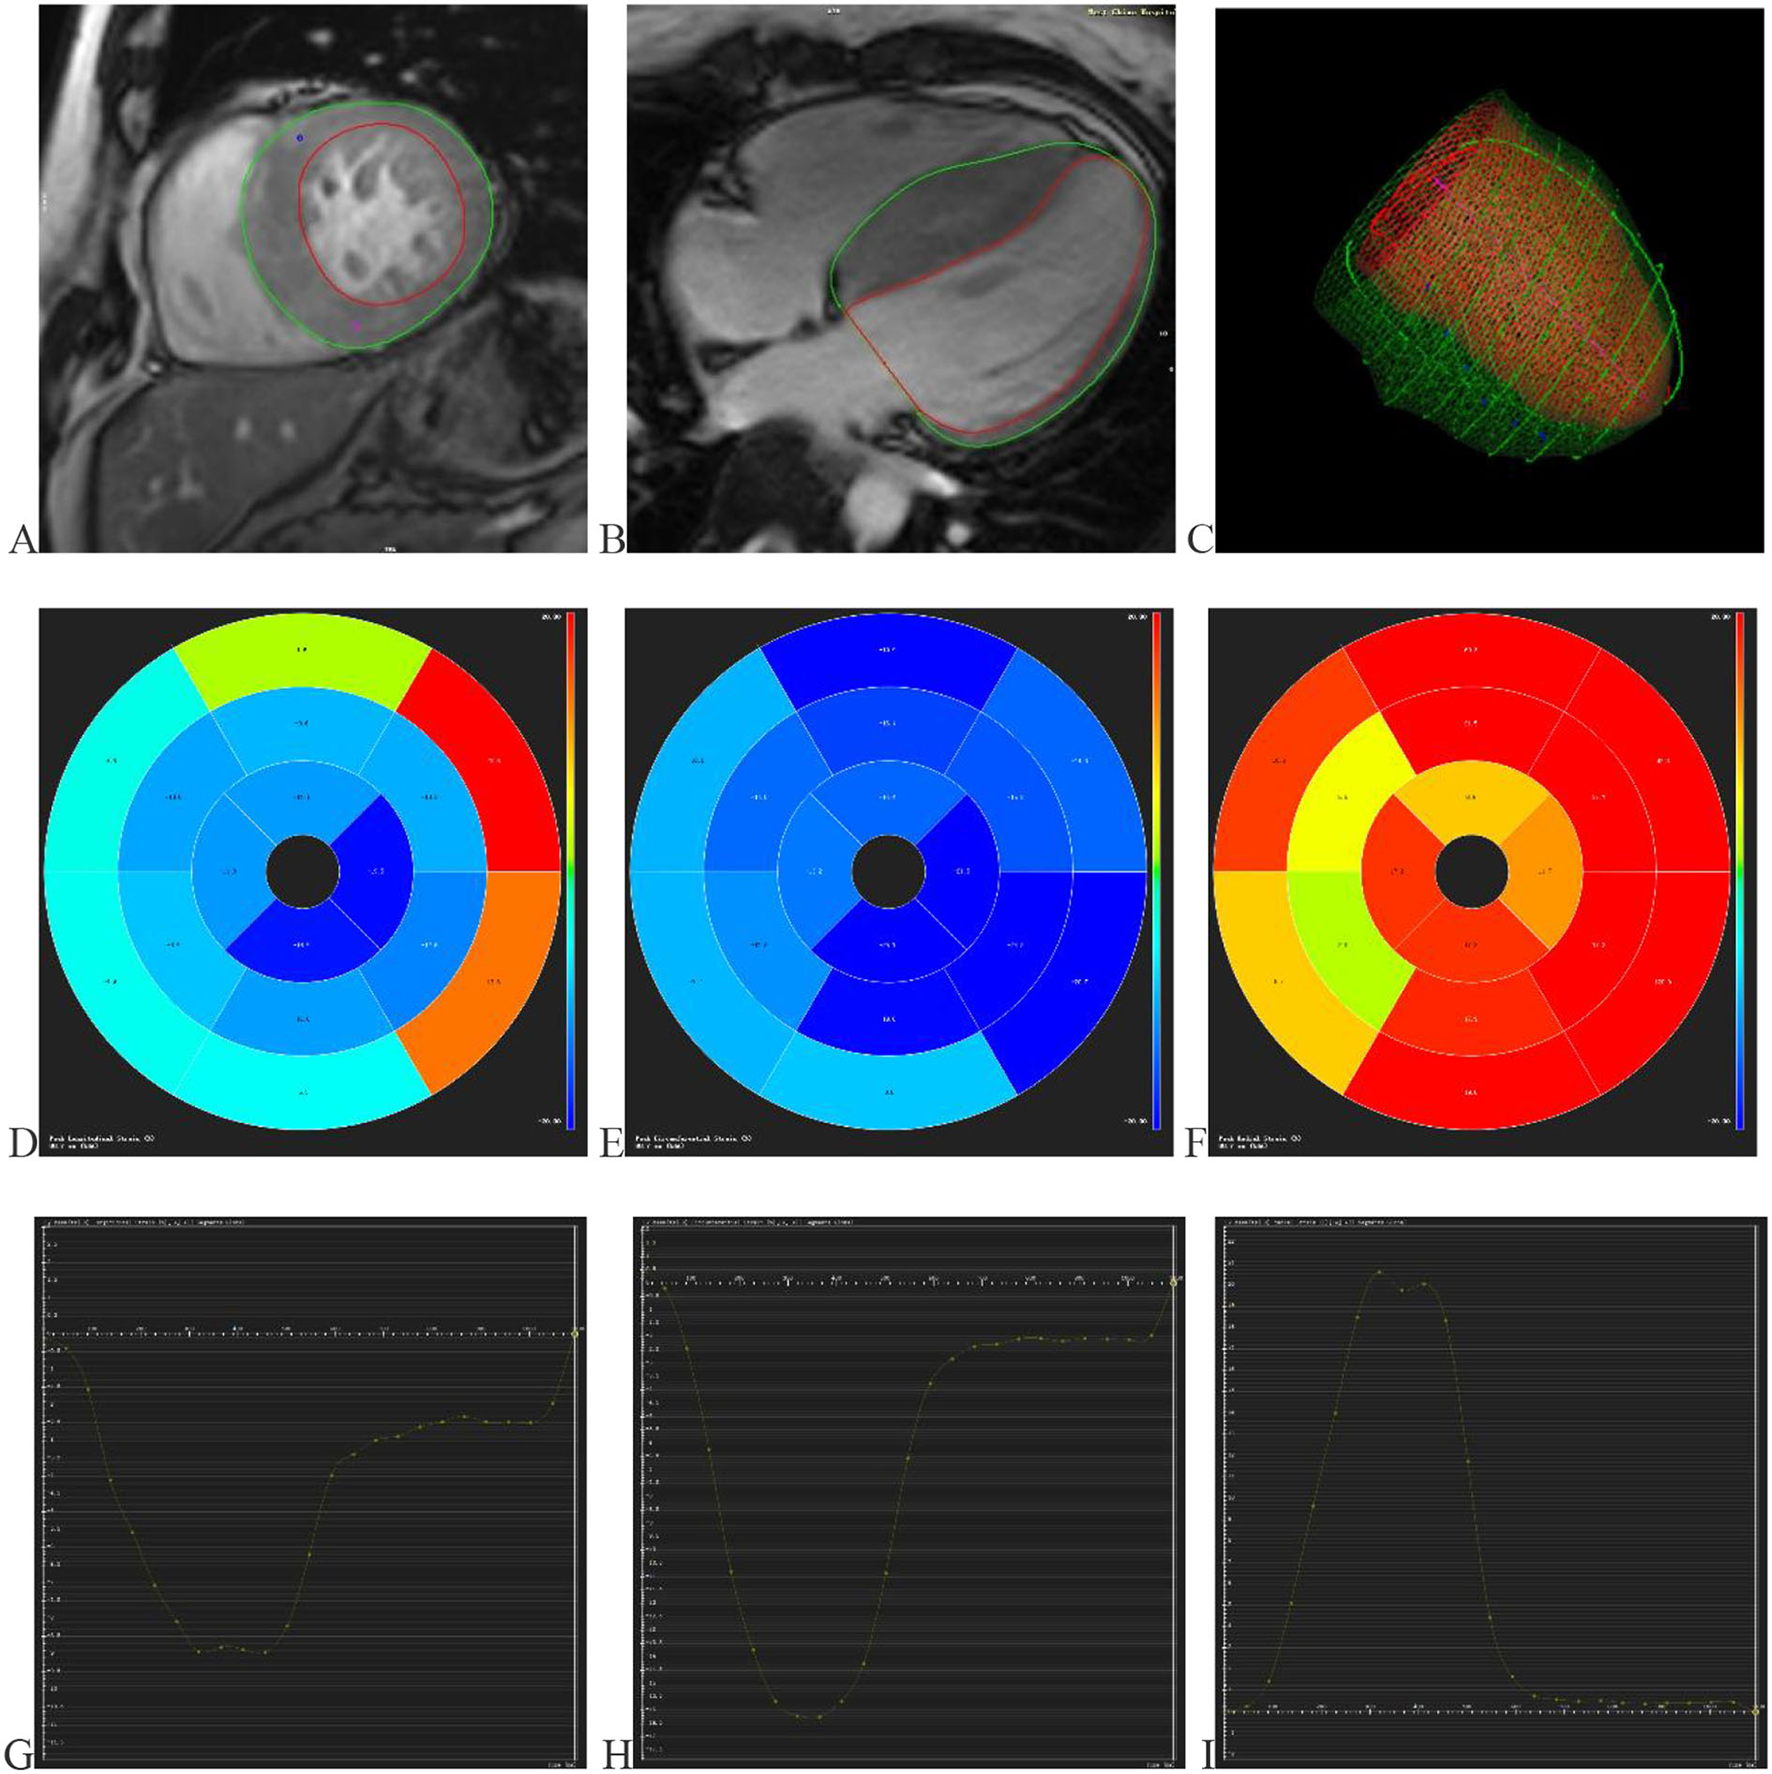

Two radiologists conducted CMR data analysis with over 5 years of experience in imaging analysis. When they differed in opinion, they would negotiate with each other to achieve a consensus. The CMR image data acquired from the scanning workstation were loaded in software named “CVI.42” (Circle Cardiovascular Imaging, version 5.11, Calgary, AB, Canada) for analyzing LV function and characterization. First, a short-axis stock was dragged into the SHORT 3D module by drawing up the optimal endocardium and epicardium to acquire the basic cardiac function parameters, including LVEF, end-diastolic volume, end-systolic volume, and stroke volume. Meanwhile, a cardiac cycle measured maximum left ventricle wall thickness (MLVWT) during the end of diastole. Second, 2- and 4-chamber long-axis views and a set of short-axis views were transmitted into the Feature Tracking module. The optimal endocardium and epicardium were drawn up, excluding papillary muscles (Figure 1). Then CVI.42 would automatically calculate the cardiac strain parameters such as global and segmental strains (Figure 1). LV contractility was evaluated by global radial strain (GRS), global circumferential strain (GCS), global longitudinal strain (GLS), apical radial strain (ARS), apical circumferential strain (ACS), apical longitudinal strain (ALS), mid-ventricular radial strain (MRS), mid-ventricular circumferential strain (MCS), mid-ventricular longitudinal strain (MLS), basal radial strain (BRS), basal circumferential strain (BCS), and basal longitudinal strain (BLS).

Figure 1

Displays the progress and outcomes of LV strains. (A) Delineating the LV endocardium and epicardium in the short-axis view. (B) Delineating the LV endocardium and epicardium in the 4-chamber long axis view. (C) The optimal endocardium and epicardium are shown in 3D space. The segmental strain round cake is mapped into 16 sections in the circumferential (D), longitudinal (E), and radial (F) directions. The global circumferential (G), longitudinal (H), and radial (I) strain curves in one cardiac cycle. LV (left ventricular).